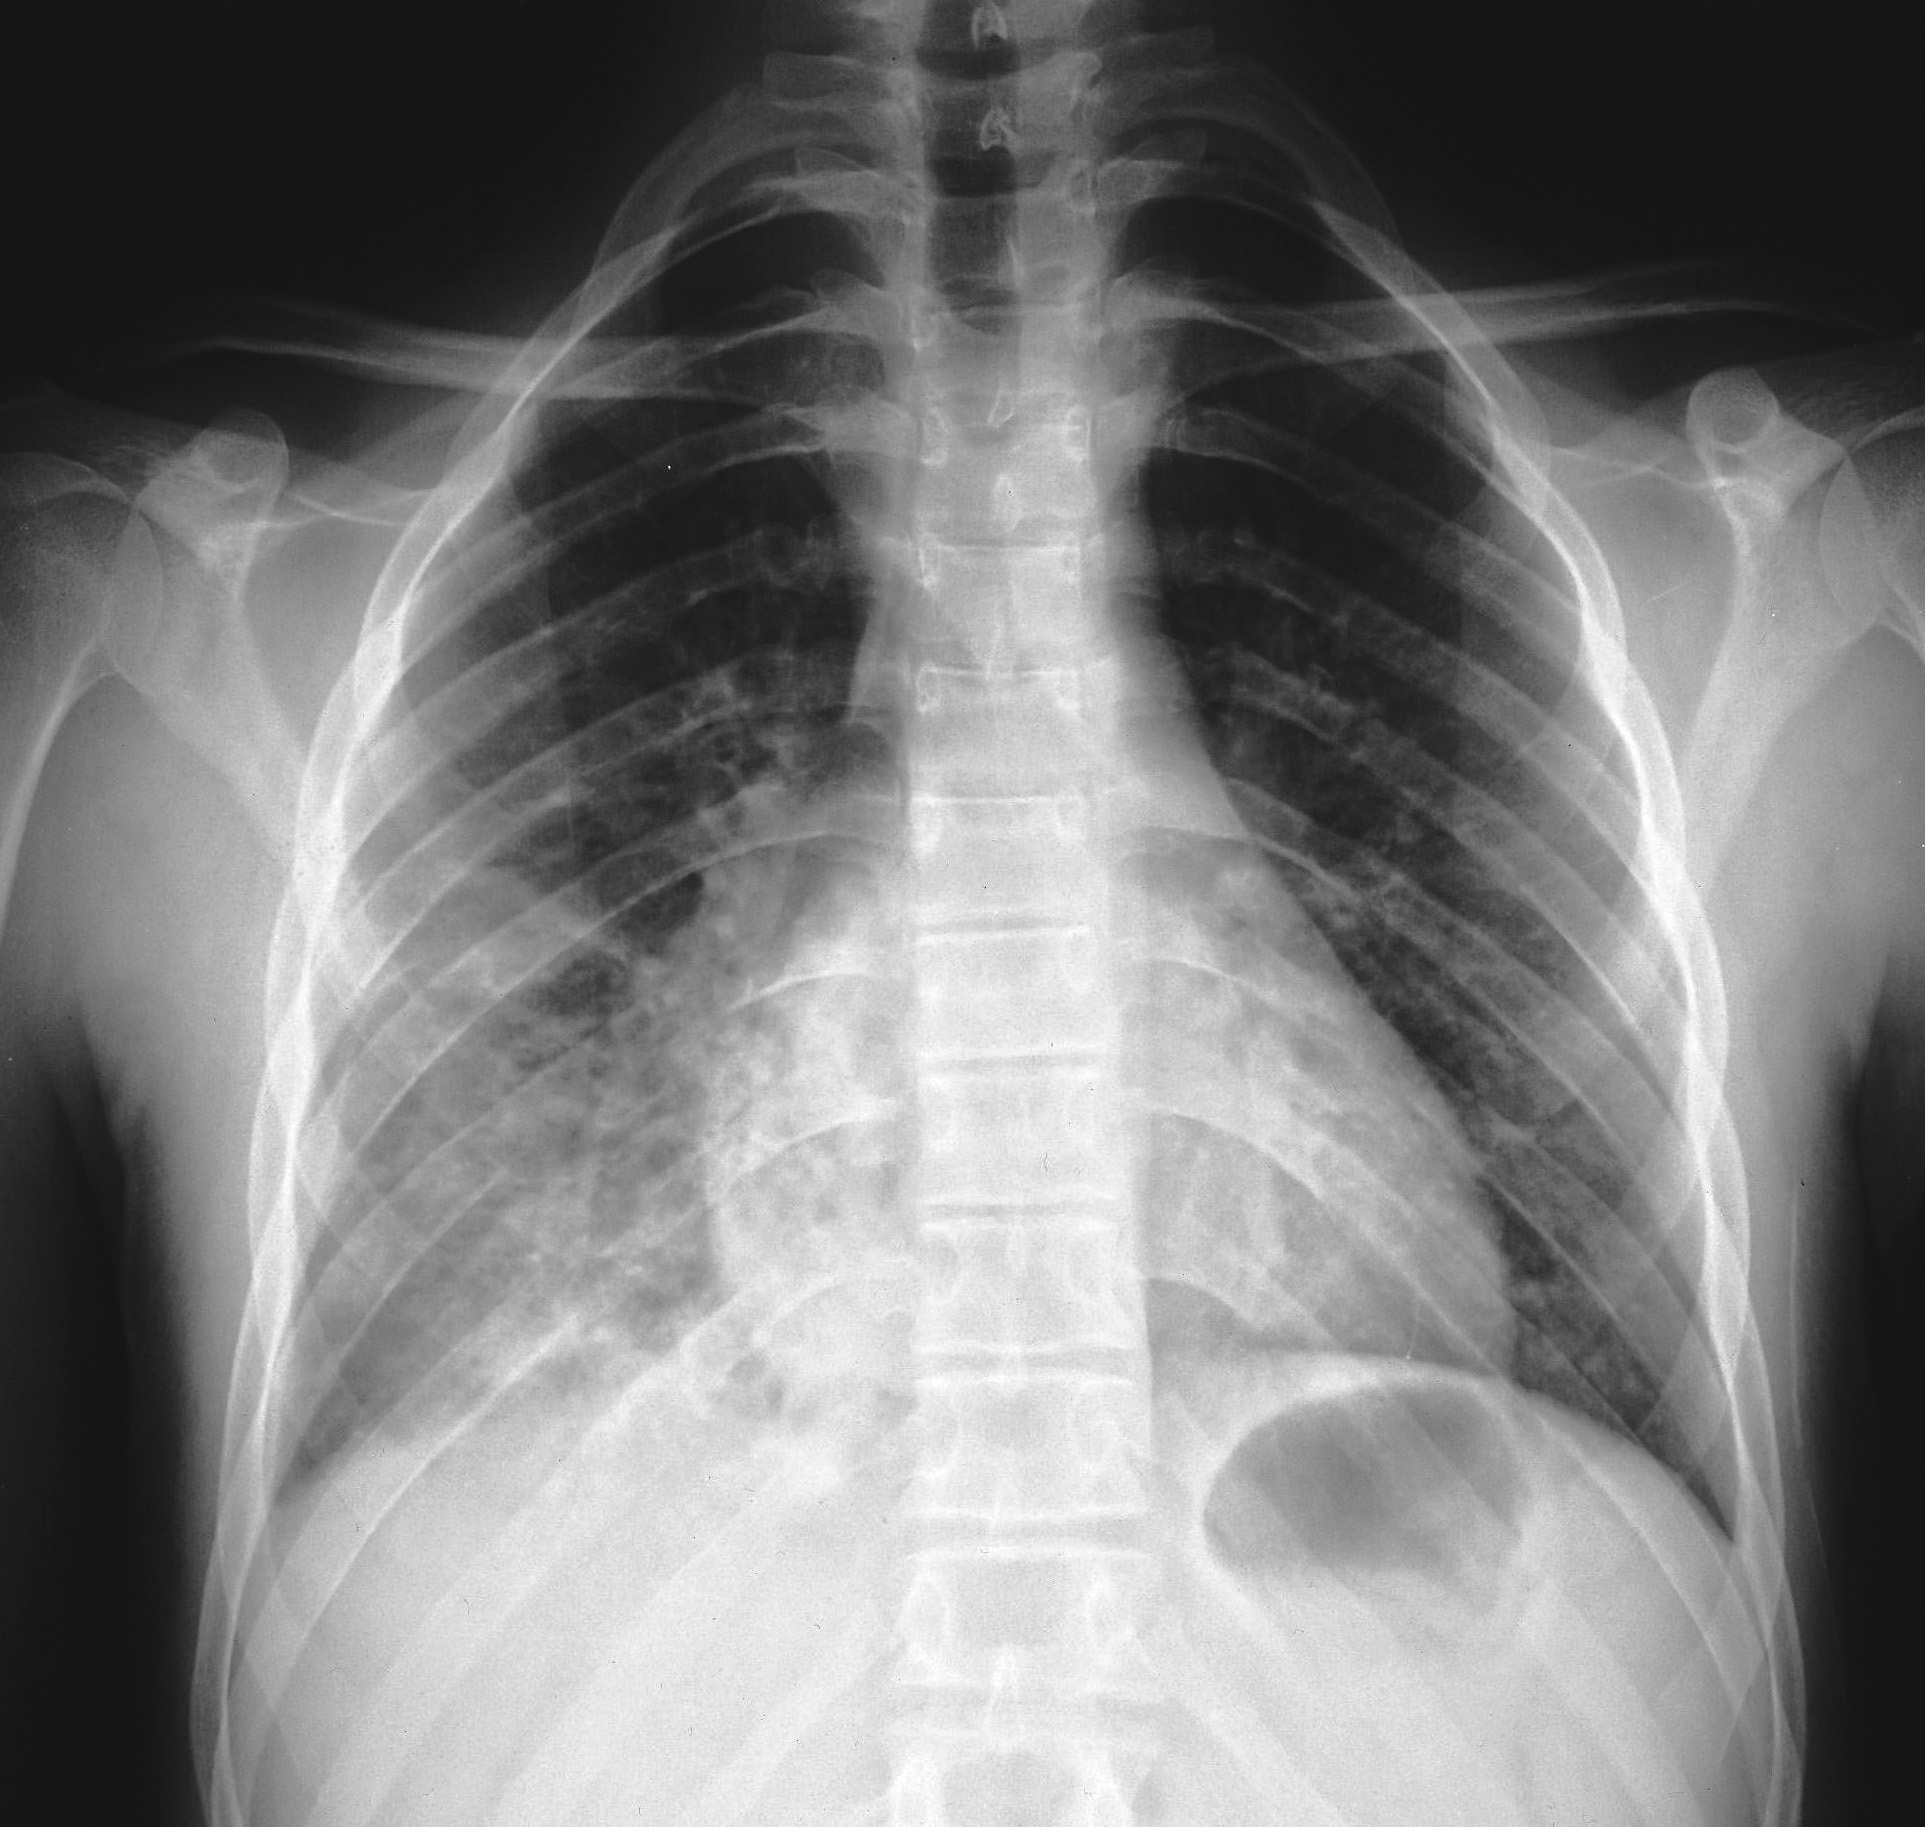

Nel complesso, cinque pazienti hanno presentato gastro-enterite con severa disidratazione, quattro bronco-polmonite con crisi dispnoiche, due bronco-ostruzione con crisi di cianosi, uno impetiginizzazione delle lesioni cutanee e, infine, un paziente congiuntivite purulenta. I pazienti italiani hanno presentato una maggiore percentuale di complicanze rispetto ai pazienti rom (Figura 2). Tra i pazienti italiani, due hanno presentato gastro-enterite mentre tre hanno sviluppato una broncopolmonite, confermata dalla radiografia del torace (Figura 3). Il bambino di un mese � stato trattato con immunoglobuline e.v. Nessun paziente ha presentato complicanze neurologiche.

Figura 3a. |

Figura 3b. |

Figura 3. Radiogramma del torace in proiezione antero-posteriore (a) e latero-laterale (b) in un paziente italiano di 15.3 anni. � evidente una polmonite interstiziale bilaterale, pi� accentuata a dx, con obliterazione dello spazio retrocardiaco, diagnosticata dopo 2 giorni dalla comparsa dell'esantema.